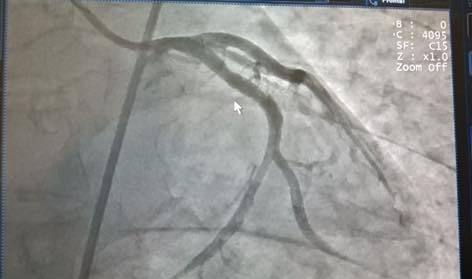

Do có sự chuẩn bị và phối hợp từ trước, bệnh nhân nhanh chóng được chuyển thẳng về Đơn vị Can thiệp mạch để chụp động mạch vành, kết quả là tổn thương tắc hoàn toàn động mạch liên thất trước, huyết khối lấp đầy động mạch. Sau 20 phút căng thẳng, ê kíp các bác sĩ đã hồi sức cấp cứu và can thiệp thành công, lấy huyết khối, đặt stent tái thông động mạch cứu sống bệnh nhân.

Hình ảnh chụp động mạch vành của bệnh nhân trước can thiệp